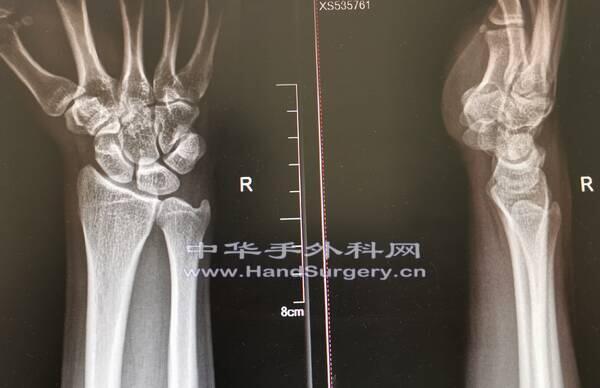

今天上午门诊,一个21岁大学生来测骨龄

看看还能不能长个儿

现在168cm

拍照腕关节正侧位和膝关节正侧位片

你们看看他还能再窜一窜吗